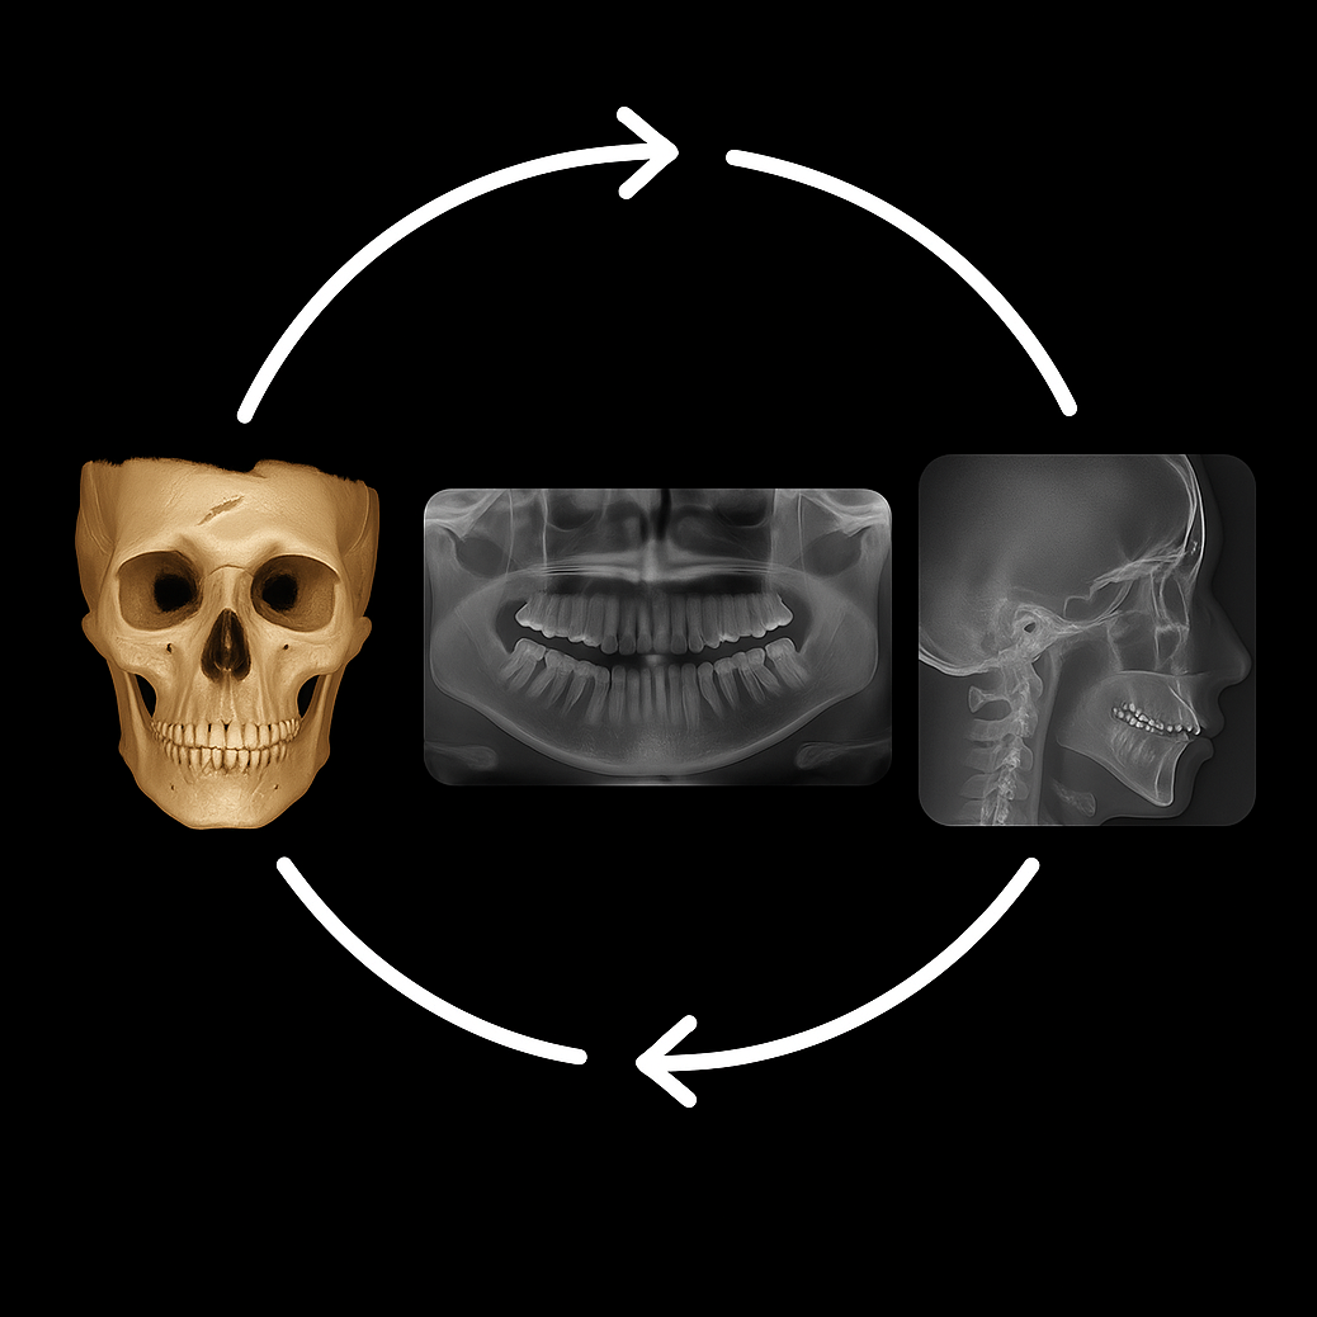

One Scan All You Need

Capture high quality CBCT, panoramic, and cephalometric images in a single scan.

No retakes. No extra radiation. Improved patient experience without compromising quality.